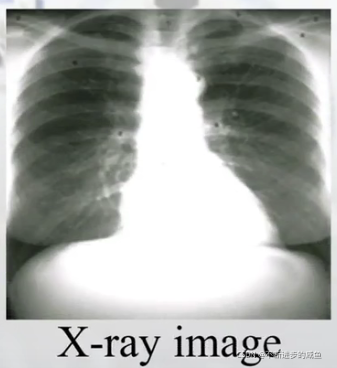

(3)X-ray图像:很好描述肺结构